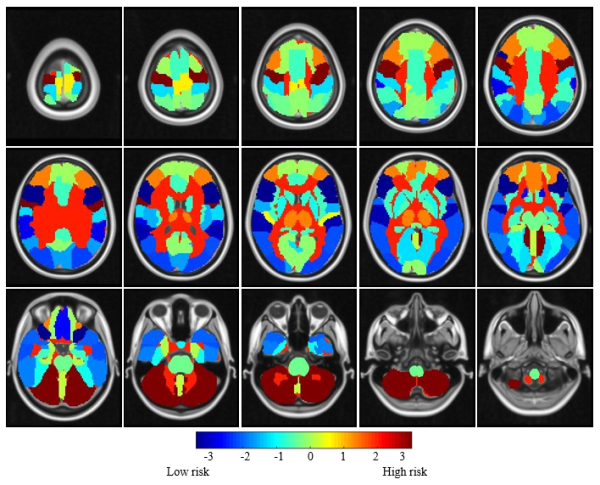

前期,中国科学院苏州生物医学工程技术研究所联合山东省肿瘤医院,采用医学图像配准和统计检验方法构建了小细胞肺癌脑转移风险图谱,(图1,Cancer Imaging,https://doi.org/10.1186/s40644-021-00410-w)。在此基础上,科研人员针对前期研究未探索非小细胞肺癌患者脑转移瘤空间分布的问题,扩大研究队列,纳入全国3家医院的728例确诊脑转移的肺癌患者,在患者的脑磁共振影像数据上共标注2997个转移灶,借助配准技术将所有转移灶映射到标准脑模板上,通过脑区地图集将标准脑模板自动划分为41个脑区,从而统计每个脑区的转移概率,并运用医学统计检验方法对比每个脑区的转移概率与预期转移概率的差异,最终确定每个脑区的转移风险水平(非小细胞肺癌脑转移风险图谱,图2)。

研究显示,小脑(运动调节中枢)在两种肺癌亚型中均为高风险脑区,丘脑(触觉和温痛觉)、杏仁核(情绪和学习功能)和海马旁回(记忆视觉场景)在两种肺癌亚型中均为低风险脑区。此外,非小细胞肺癌患者的中央旁小叶(控制排便和排尿)、额中回(书写功能)和中心前回(控制对侧半身的运动)是高风险脑区。

图1.小细胞肺癌脑转移风险图谱,脑区颜色越红表示该区域的转移风险越高,脑区颜色越蓝则表示该区域的转移风险越低。

图2.非小细胞肺癌脑转移风险图谱